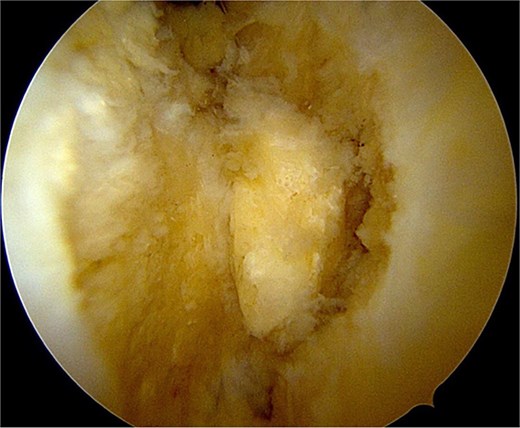

After partial resection of the infrapatellar fat pad for better visualization, the ossicle was exposed by finding the spinal needle and working around it. The fragment was freed arthroscopically using a motorized shaver and a radiofrequency probe (Fig. 5), taking care to protect the patellar tendon.

Once the ossicle was mobile and free (Fig. 6), it was removed either in one piece or was broken into multiple pieces with an arthroscopic burr and then removed with a grasper (Figs 7 and 8). Finally, the tibial tubercle was leveled using either an arthroscopic burr or shaver.

Arthroscopic views of case 1. (A) Ossicle fragment removed. Case 2 (B) tibial tubercle leveling using an arthroscopic Burr. Case 3 (C) ossicle fragment removed.